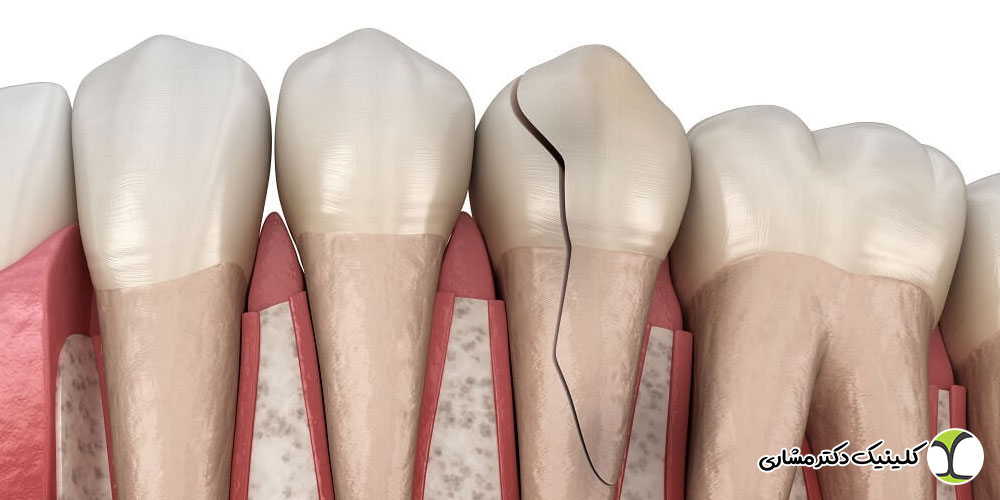

۲. تحلیل استخوان: تحلیل استخوان میتواند بر اثر:

- شکست درمانهای ریشه

- آبسههای دندانی

تحلیل استخوان فرایندی طبیعی است که پس از کشیدن دندان آغاز میشود. هرچه جای دندان مدت بیشتری خالی بماند، استخوان ناحیه سریعتر جذبشده و ضعیف میشود. عفونتهای ریشه درماننشده نیز میتوانند باعث تخریب شدید استخوان شوند؛ موضوعی که اندودونتیستها بیش از سایر متخصصان با آن مواجهاند.

در بسیاری از بیماران، تحلیل استخوان نتیجه عفونتهای قدیمی ریشه یا درمان ناکامل کانال است. اندودونتیست میتواند:

- التهابهای زیر لثه و آسیبهای استخوانی ناشی از آبسه را ارزیابی کند